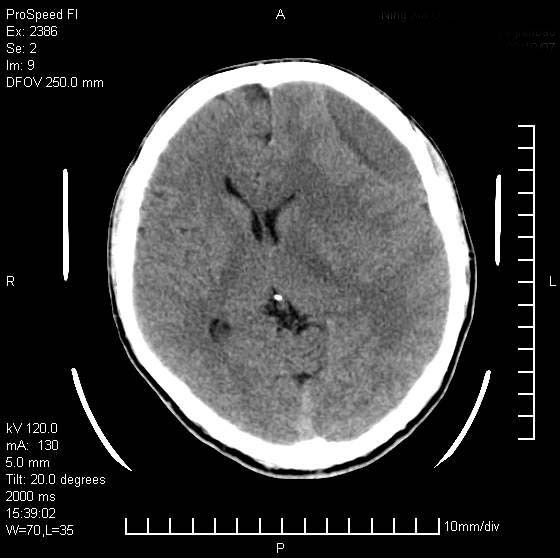

以下是引用天南地北在2007-9-19 18:43:00的发言:[br]典型慢性硬膜外血肿[br][br][本贴已被 天南地北 于 2007-9-19 18:44:11 修改过]

以下是引用曼一拍在2007-9-20 11:06:00的发言:[br]支持慢性硬膜下血肿.[br]慢性硬膜下积液:血肿有包膜,ct值稍高于脑脊液,增强可有染色。不典型者血肿可多呈梭形.是硬脑膜与蛛网膜之间的潜在腔隙内的血肿。[br]鉴别:[br]1\\硬膜外血肿:是颅脑外伤后脑膜或板障内血管破裂,血液在颅骨与硬膜之间积聚所致.通常是脑膜动脉破裂,也可因静脉窦破裂或颅骨的板障静脉出血,发生于外伤的着力部,常与颅骨骨折并存。脑膜动脉出血则急,若是板障静脉出血在则可有慢性。[br]2\\硬膜下积液:(硬膜下水瘤)[br]是由于蛛网膜破裂,脑脊液经蛛网膜破口进入硬膜下腔不能回流。或水肿阻塞而形成。[br]ct表现:颅骨内板下方新月形低密度区近似脑脊液密度;占位效应清,周围无脑水肿。[br]